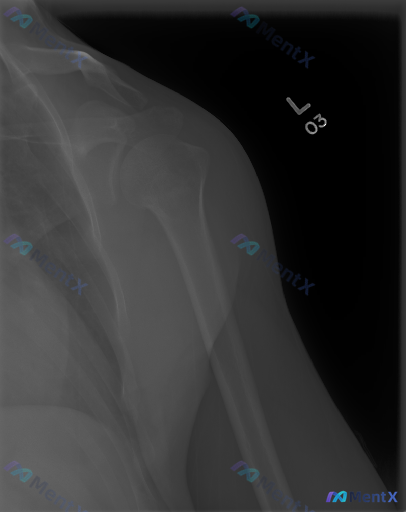

这张左肩X光片看着完全正常,但患者有症状,你会怎么想?

整理了一份左侧肩部正位X光片的资料,先看影像表现: - 肱骨近端、肩胛骨、锁骨远端骨皮质连续,未见明确骨折线/脱位 - 骨密度均匀,无明显骨质破坏或硬化 - 盂肱关节、肩锁关节间隙正常,无明显骨赘形成 - 肩周软组织无明显肿胀,冈上肌腱止点附近未见明确钙化灶 简单说:单看这份X光,骨性结构基本是“阴...